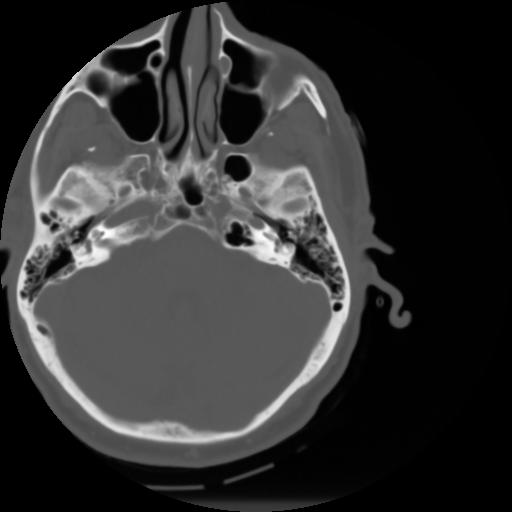

3 CEREBRO,,Axial,3.0,CEREBRO,,